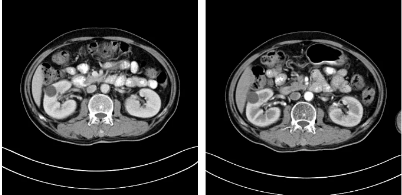

据安图叔叔的儿子回忆道,安图叔叔在体检前没有发现任何不适的症状,在体检后才知双肾占位,右肾下级占位16.1*7.2cm,左肾下级肿瘤约3.7*4.3cm的情况。突如其来的病情让一家人陷入了恐慌,从未想过一个健康自律的人会突然间就被检出肾癌,还是双肾。安图叔叔的儿子激动地说道:“我当时一下子懵了,父亲之前表现那么健康,一查竟病得很重,为确诊我把父亲转接到新加坡就诊,那边的医生在看了我父亲的片子后都表示这是肿瘤,要做切除双肾然后再透析,对于我们来说,切肾这样的治疗方案对我们来说是无法接受的,父亲毕竟一把年纪,这样做法太伤他身体。”

2017年9月安图叔叔开启新治疗之路,入院检查发现安图叔叔右肾透明细胞癌T3NxM1IV期、左肾癌、纵隔淋巴结转移瘤。为缓解安图叔叔腰疼的状况,9月21日进行介入治疗。经复大专家认真探讨后,考虑到安图叔叔身体精神状态良好,可进行冷冻消融术。经专家解说和安慰后,安图一家悬着心终于放下了。

2017年9月29日,从CT影像看到右肾情况更为严重。为减缓肿瘤增长的速度,专家进行商议后,最终决定由牛立志教授主刀为安图叔叔进行了右肾肿瘤冷冻消融术。手术开始后,牛立志教授在CT和超声引导下,同时使用两根冷冻针固定病灶,精准灭活肿瘤;术后很成功无不良反应。术后一周进行第二次双肾肿瘤冷冻消融术。安图叔叔儿子笑道:“当时真的很紧张,医生劝慰我无须担心,都交给他们,我们都很清楚知道父亲的病情,真的很感谢也很庆幸我父亲遇到复大的医护人员,免受开刀之痛。住院期间医护人员很尽心尽力的照顾父亲,手术的成功离不开他们的辛劳付出。”